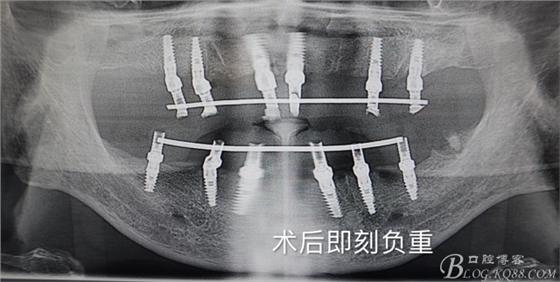

首頁牙科種植 四塊導板.全口種植.即刻負重

四塊導板.全口種植.即刻負重